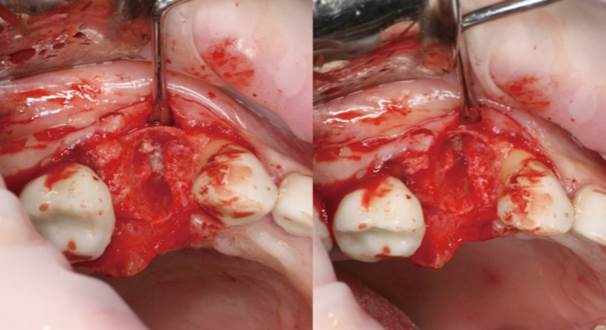

Clinical case: Extraction, immediate implant placement, & provisionalization

- Courtesy of Dr. Iulian Filipov, Romania -

Keywords

AnyRidge, R2GATE, guided surgery, immediate placement, immediate provisionalization, initial stability, Dr. Iulian Filipov, #25, maxillary posterior, immediate loading, Mega ISQ

Products:

AnyRidge implant system, R2GATE, MEGA ISQ, Digital prosthesis